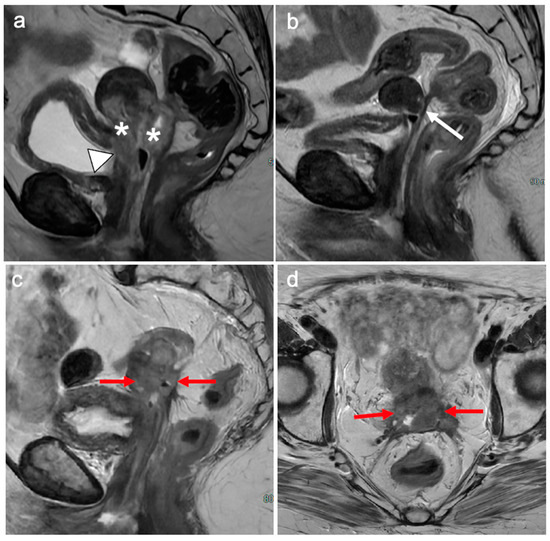

6. FIGO Stage III

7. FIGO Stage IV

- Valentini, A.L.; Gui, B.; Miccò, M.; Giuliani, M.; Rodolfino, E.; Ninivaggi, V.; Iacobucci, M.; Marino, M.; Gambacorta, M.A.; Testa, A.C.; et al. MRI anatomy of parametrial extension to better identify local pathways of disease spread in cervical cancer. Diagn. Interv. Radiol. 2016, 22, 319–325. [Google Scholar] [CrossRef]

- Freeman, S.J.; Aly, A.M.; Kataoka, M.Y.; Addley, H.C.; Reinhold, C.; Sala, E. The revised FIGO staging system for uterine malignancies: Implications for MR imaging. Radiographics 2012, 32, 1805–1827. [Google Scholar] [CrossRef] [PubMed]

- Kostov, S.; Selçuk, I.; Watrowski, R.; Kornovski, Y.; Yalçın, H.; Slavchev, S.; Ivanova, Y.; Dzhenkov, D.; Yordanov, A. Pelvic Sidewall Anatomy in Gynecologic Oncology-New Insights into a Potential Avascular Space. Diagnostics 2022, 12, 519. [Google Scholar] [CrossRef]

- Miccò, M.; Lupinelli, M.; Mangialardi, M.; Gui, B.; Manfredi, R. Patterns of Recurrent Disease in Cervical Cancer. J. Pers. Med. 2022, 12, 755. [Google Scholar] [CrossRef] [PubMed]